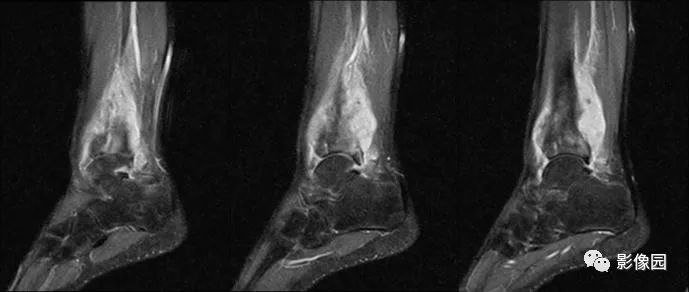

【影像学检查】2016-01-05

评论:前片X线示左胫骨下段及干骺端病变,髓腔内密度不均匀增高,内侧骨皮质可见骨质破坏,可见骨膜反应。CT示病灶内见多发斑片状肿瘤骨(黄色箭头),周围可见针状骨膜反应(红色箭头)。周围软组织肿胀。MRI示胫骨下段以长T1、长2信号为主的混杂信号影,未跨越胫距关节面,周围未见明显软组织肿块。周围软组织广泛片状长T1长T2信号影。复查X线示病变较前片明显进展,左侧胫骨远段及干骺端骨质破坏,周围可见针状骨膜反应及Codman三角(蓝色箭头)形成。相邻左侧腓骨下端、距骨滑车受累。